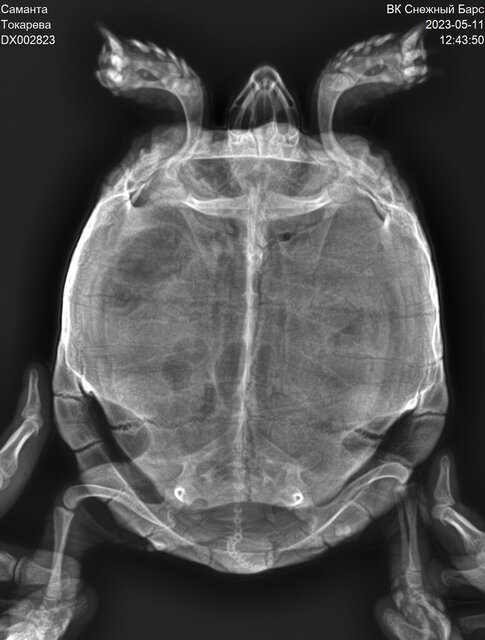

Среднеазиатская , самка, предположительно 10-15 лет

Вес 1 кг, около 20 см

Розовых пятен стало больше, пропали белые выделения. Есть биохимия крови и рентген на руках. Пожалуйста, скажите какая у нас сейчас ситуация

Ситуация следующая : нам назначили регулярные продолжительные теплые ванны. Если до конца месяца выделения не появятся, то поедем на промывание мочевого пузыря. Если после данной манипуляции не будет положительной динамики, то назначат операцию на мочевом в виду возможных нерентгенконтрастных камней.

@Дина_ меня смутил то что показатель ЩФ достаточно высокий (662) , Мочевая кислота 272

Остальные показатели низкие

Нам же сказали что это показатели в норме

Анализы и рентген на руках. Мне бы узнать какие прогнозы в действительности